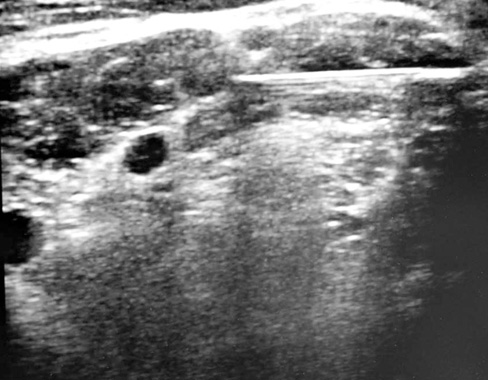

脊髄神経根が椎間孔から脊柱管外にでた部位でブロックする方法です。内服などで改善がみられないような強い神経痛を生じている場合に行います。診断と治療を兼ね備えたすぐれた神経ブロックです。腰椎ではうつぶせで、レントゲン透視をみながら行います。頚椎では仰向けで、超音波装置(エコー)をみながら行います。所要時間は10-15分程度です。

使用する針は細いものを使用するため皮膚への刺激は少ないですが、神経根のそばに針をすすめるためときどき神経組織を刺激することがあります。

頚椎神経根ブロック